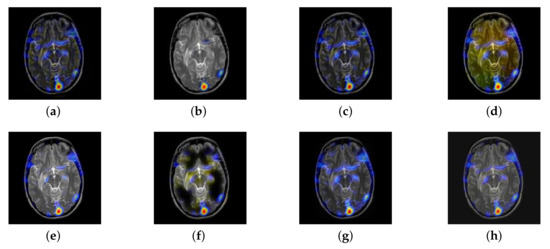

In this section, there are four image sets to fuse, each containing a MRI image and its corresponding CBF image in Figure 41. In Figure 42, Figure 43, Figure 44 and Figure 45, it can be seen that the structural information of fusion images obtained by our algorithm is complete. The color is not distorted, and the spectral features are natural. The fusion image based on DTCWT and NSCT algorithm have high color fidelity but less structural information. Other algorithms, such as IGM, LPSR, and FusionCNN, only focus on the structural information of the MRI image and ignore the color information of the fused image. Although the image structure information obtained by DDcGAN fusion algorithm is relatively complete, the edge of color information is not clear, which has a great influence on image contrast.

Figure 41.

Four pairs of MRI-cerebral blood flow diagram (CBF) source images: (a,c,e,g) are MRI images; (b,d,f,h) are CBF images.

Figure 42.

Fused medical images obtained by different algorithms (Figure 41a,b): (a) DTCWT, (b) GFF, (c) NSCT, (d) LPSR, (e) IGM, (f) FusionCNN, (g) DDcGAN, and (h) FusionNet.

Figure 43.

Fused medical images obtained by different algorithms (Figure 41c,d): (a) DTCWT, (b) GFF, (c) NSCT, (d) LPSR, (e) IGM, (f) FusionCNN, (g) DDcGAN, and (h) FusionNet.

Figure 44.

Fused medical images obtained by different algorithms (Figure 41e,f): (a) DTCWT, (b) GFF, (c) NSCT, (d) LPSR, (e) IGM, (f) FusionCNN, (g) DDcGAN, and (h) FusionNet.

Figure 45.

Fused medical images obtained by different algorithms (Figure 41g,h): (a) DTCWT, (b) GFF, (c) NSCT, (d) LPSR, (e) IGM, (f) FusionCNN, (g) DDcGAN, and (h) FusionNet.